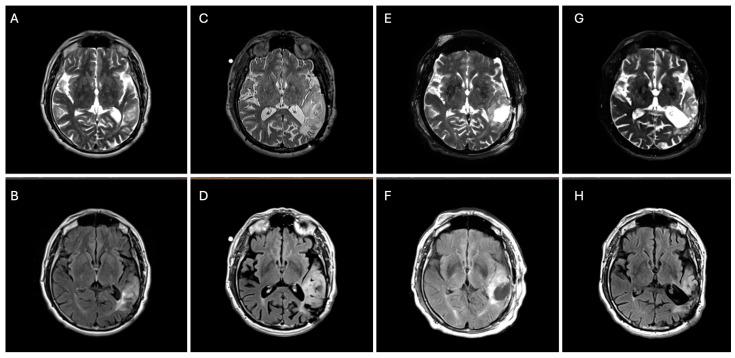

: Anaplastic oligodendrogliomas (AOs) are central nervous system (CNS) World Health Organization (WHO) grade 3 gliomas characterized by isocitrate dehydrogenase (IDH) mutation (m)IDH and 1p/19q codeletion. AOs are typically treated with surgery and chemoradiation. However, chemoradiation can cause detrimental late neurocognitive morbidities and an accelerated disease course. The recently regulatory-approved vorasidenib, a brain-penetrating oral inhibitor of IDH1/2, has altered the treatment paradigm for recurrent/residual non-enhancing surgically resected CNS WHO grade 2 mIDH gliomas. Though vorasidenib can delay the time to chemoradiation for grade 2 gliomas, the implications for vorasidenib in non-grade 2 mIDH gliomas are not well understood. We present a case of a 71-year-old male with a grade 3 non-enhancing oligodendroglioma successfully treated with vorasidenib with an 11% reduction in residual tumor volume. Vorasidenib was well tolerated in our patient with a mild elevation in his liver transaminases that resolved following a brief interruption in treatment. Our case suggests that vorasidenib may impart therapeutic benefits in this setting. This case illustrates the need for further investigation into these less commonly addressed scenarios and treatment strategies that extend beyond current guidelines.

间变性少突胶质细胞瘤(AO)是世界卫生组织(WHO)3级中枢神经系统(CNS)胶质瘤,其特征为异柠檬酸脱氢酶(IDH)突变(mIDH)和1p/19q共缺失。AO通常采用手术及放化疗进行治疗。然而,放化疗会导致有害的迟发性神经认知并发症以及疾病进程加速。最近获得监管批准的伏立西尼是一种可穿透血脑屏障的IDH1/2口服抑制剂,它改变了复发性/残留性非强化型手术切除的WHO 2级CNS mIDH胶质瘤的治疗模式。虽然伏立西尼可以延迟2级胶质瘤的放化疗时间,但对于非2级mIDH胶质瘤中伏立西尼的影响尚不清楚。我们报告了一例71岁男性3级非强化型少突胶质细胞瘤患者,使用伏立西尼成功治疗,残余肿瘤体积减少了11%。我们的患者对伏立西尼耐受性良好,仅出现轻度肝转氨酶升高,在短暂中断治疗后恢复正常。我们的病例表明伏立西尼在这种情况下可能具有治疗益处。该病例说明有必要对这些较少涉及的情况以及超出当前指南的治疗策略进行进一步研究。